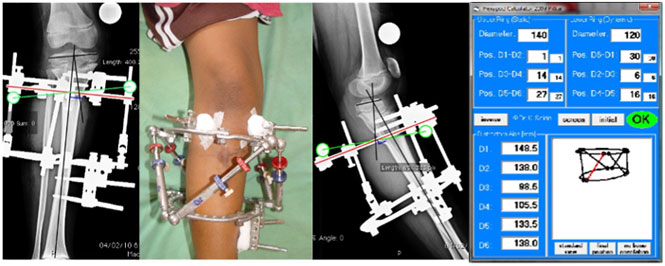

| This young girl from Nigeria had a complex deformity of the upper tibia. There was a valgus (outward bend), recurvatum (forward bend) and internal rotation (in-toeing – the foot faces inwards when the knee cap is facing is facing forward). |

| The correction was done using Hexapod external fixator system – which is a six-axis correction system. Six struts are connected to the Ilizarov ring fixator and the values are entered in a computer software. The software then gives a program on the correction process. The picture on extreme right is a screenshot of the software. The picture in the center (second from left) shows the fixator with Hexapod struts. |